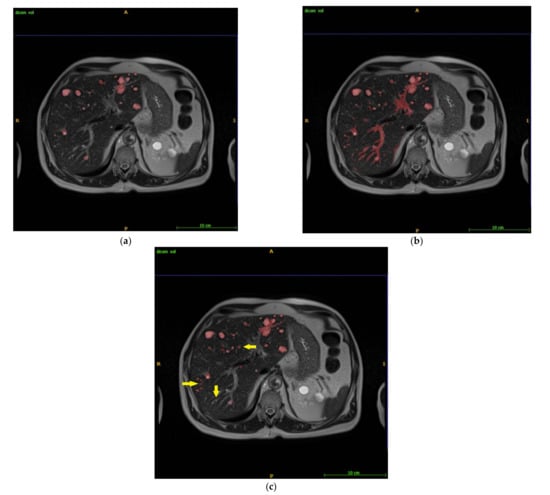

Figure 1 illustrates an example of manual liver cyst segmentation by manual GT (Figure 1a), automated LS segmentation (Figure 1b), and IRIS (Figure 1c). The substantial LS error of including vasculature and bile ducts was rapidly removed using antiSmartClick (Figure 1b vs. Figure 1c). There were small cysts missed in manual GT but captured on IRIS (arrows in Figure 1c).

Figure 1.

Liver cyst segmentation by (a) manual as ground truth (GT), (b) automated level set (LS), and (c) IRIS. LS included substantial vasculature (b), which was cleaned up rapidly using antiSmartClick (c). Small cysts missed on manual GT were captured on IRIS (arrows in (c)).

The discrepancies between manual GT, automated LS, and IRIS segmentations were reviewed and were largely caused by voxels at cyst edges and/or in spaces between neighboring cysts that were easily included in manual segmentation, as illustrated by arrows in Figure 4 and also subtly noticeable on Figure 1.

It should be noted that manual segmentation is not a perfect ground truth. Small cysts can be missed on manual segmentation because it is so tedious and tiring, as exemplified in Figure 1. The largest normalized volume error (38.7%) occurred in a case with a small liver cyst volume (13 mL by manual segmentation and 8 mL by IRIS) and was largely caused by discrepancies at border voxels. The large absolute volume error (35.9 mL) occurred in a case with a large liver cyst volume (1538 mL by manual and 1411 mL by IRIS) and was largely caused by voxels in spaces between neighboring cysts (Figure 4). We feel that IRIS can provide a more consistent border definition for cysts and, therefore, a better ground truth.